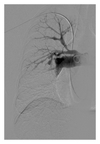

Routine laboratory examination did not show any signs of inflammation. Electrocardiogram was normal. Echocardiogram showed a thickened mitral valve, a tricuspid regurgitation of 3/4 with an estimated systolic pulmonary arterial pressure (PAP) of 60 mmHg, and a markedly dilated, mildly hypocontractile right ventricle. Right heart catherisation showed a mean PAP of 28 mmHg, a cardiac index of 2.91 L/min/m2, and a total pulmonary vascular resistance of 450 dyne.sec.cm−5. Exercise capacity was impaired as shown by a 6 min walking distance of 553 meters (69% of predicted) with desaturation from 96 to 90% and by an ergospirometry showing a peak oxygen consumption of 22 ml/min/kg with desaturation from 97 to 83%. Lung function was normal except for a low diffusion capacity of 46%. Chest X-ray showed enlarged pulmonary arteries with a right parahilar nodule, perfusion scan multiple lobar and segmental defects, and pulmonary angiography amputations of the right lower lobe and left upper lobe arteries, with multiple aneurysmal dilatations of the branches of the right upper lobe artery (Figure 1). CT of the chest confirmed the presence of a nodule in the right upper lobe, which was metabolically active on PET scan (Figure 2(a)).

In our patient, a 4-item differential diagnosis was discussed: (1) CTEPH, but angiography was somewhat atypical and pulmonary hypertension was mild; (2) Takayasu arteritis [1], but without systemic inflammation or proximal systemic artery disease at CT, MRI, and PET scans; (3) mycotic pulmonary aneurysms [2], again without systemic inflammation or chronic infection; (4) pulmonary artery intima sarcoma, but without proliferative process in central pulmonary arteries. After local as well as international multidisciplinary consultations, we initially rejected the diagnosis of pulmonary intima sarcoma and tackled the diagnosis of Takayasu disease by treating the patient with high doses of oral corticosteroids combined with ongoing anticoagulation. After 2 months of therapy, evolution was characterized by clinical deterioration with appearance of cough, brown and sometimes bloody expectorations and intermittent fever, by a slightly increased CRP (19 mg/L, <5), and by progression of the lesions on Chest X-ray (Figure 3), CT (Figure 4), and PET (Figure 2(b)) scans. The right upper lobe nodular lesion was enlarged, while a thin-walled large cavity had replaced a previously known pleural based condensation in the right lower lobe. A bronchoalveolar lavage showed aspergillus fumigates colonization and voriconazole was added to the therapy while corticosteroids were downtitrated. Retrospectively, we found evidence for infiltrates followed by infarction/cavitation also in the upper segment of the left lower lobe. As intima sarcoma of the pulmonary artery with distal embolisation was the most probable diagnosis, it was decided to perform a pulmonary endarterectomy later completed by lung resection and/or chemotherapy with tyrosine kinase inhibitors according to cell type. While the macroscopic aspect of the surgical material was suggestive for CTEPH, histopathology confirmed the diagnosis of undifferentiated intima sarcoma. In our patient the disease progressed unfortunately very rapidly after surgery with ICU readmission on day 9 because of chest pain, severe progressive hypoxemia, and hemoptysis. As CT scan showed multiple infiltrates and recurrent obstruction of the right lower lobe artery it was decided to withhold therapy. Autopsy showed (i) residual intima sarcoma in the peripheral branches of both pulmonary arteries, with complete or partial vessel wall invasion and extravascular extension (Figure 5), (ii) a myxoid nodular mass, 3 cm in diameter, in the right middle lobe, (iii) a large “cavity” with myxoid center, more specifically formed by oedematous tumoral tissue forming a lattice-like network responsible for radiolucency, in the right lower lobe. There were no signs of infection or aspergillar invasion.